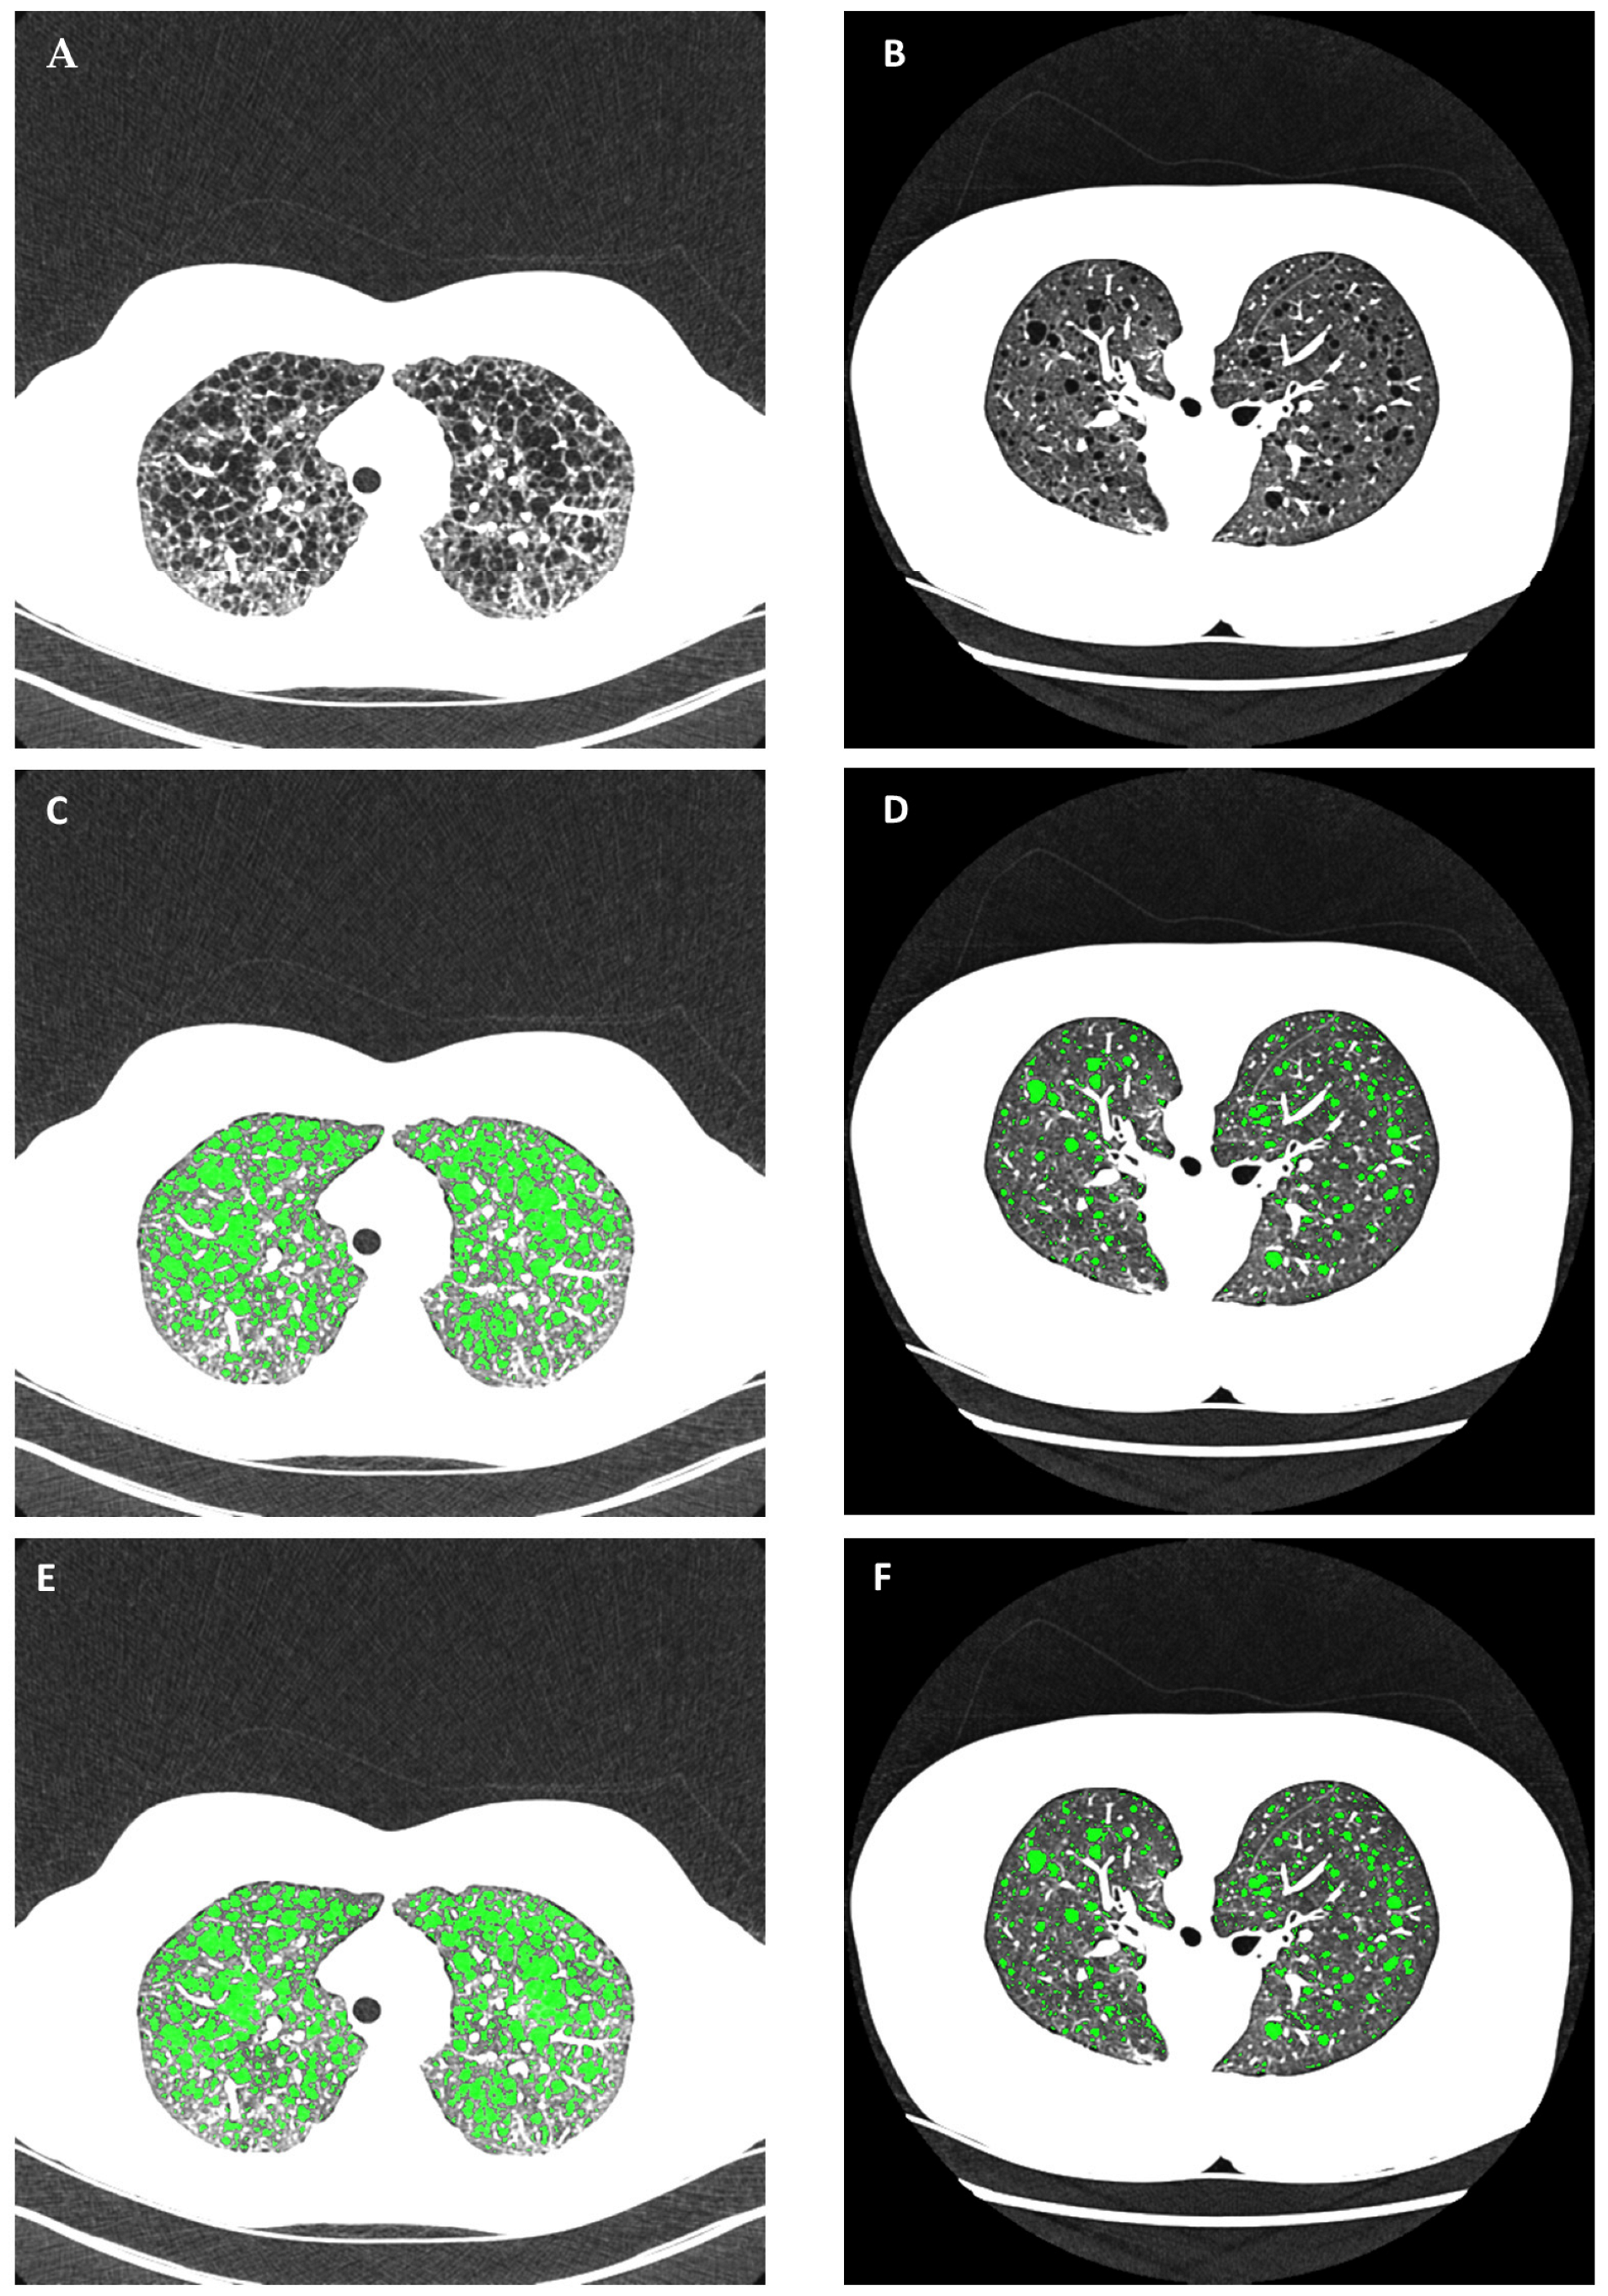

2.4. Automated Cyst Segmentation